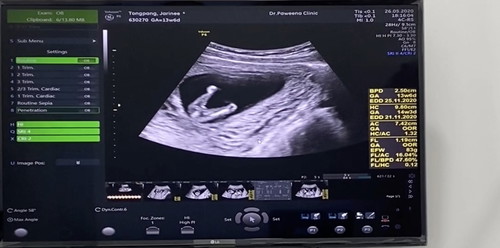

ช่วยดูหน่อยจ้า จู๋ หรือ จิ๋ม ?

ไม่ค่อยเเน่ใจค่ะ หมอว่าไงคะ จู๋รึป่าว เหมือนจะโผล่